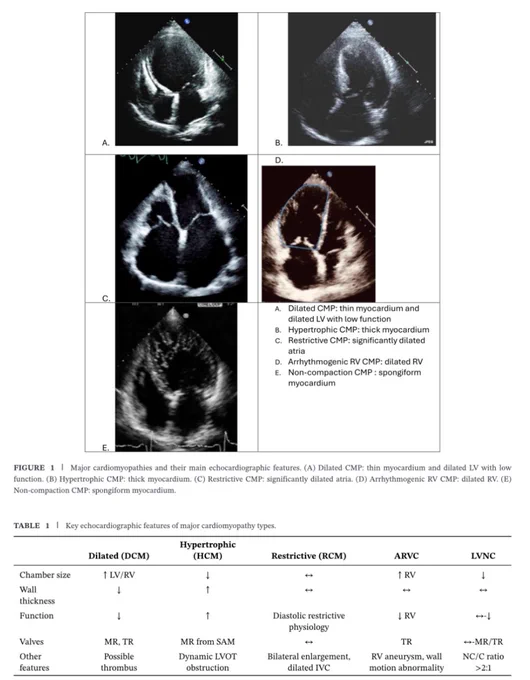

🔴 Echocardiographic Features of Cardiomyopathies: A Comprehensive Review #Cardiology #CardioEd #FOAMed #echofirst